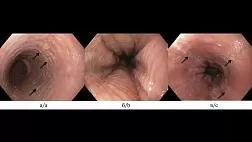

Последовательность осмотра и воспалительные изменения гортани.

• Лекция по диагностике с помощью видеоэндоскопии в практике оториноларин голога. Будут освещены вопросы обследования гортани, цели, показания и методики, а также представлены клинические случаи.